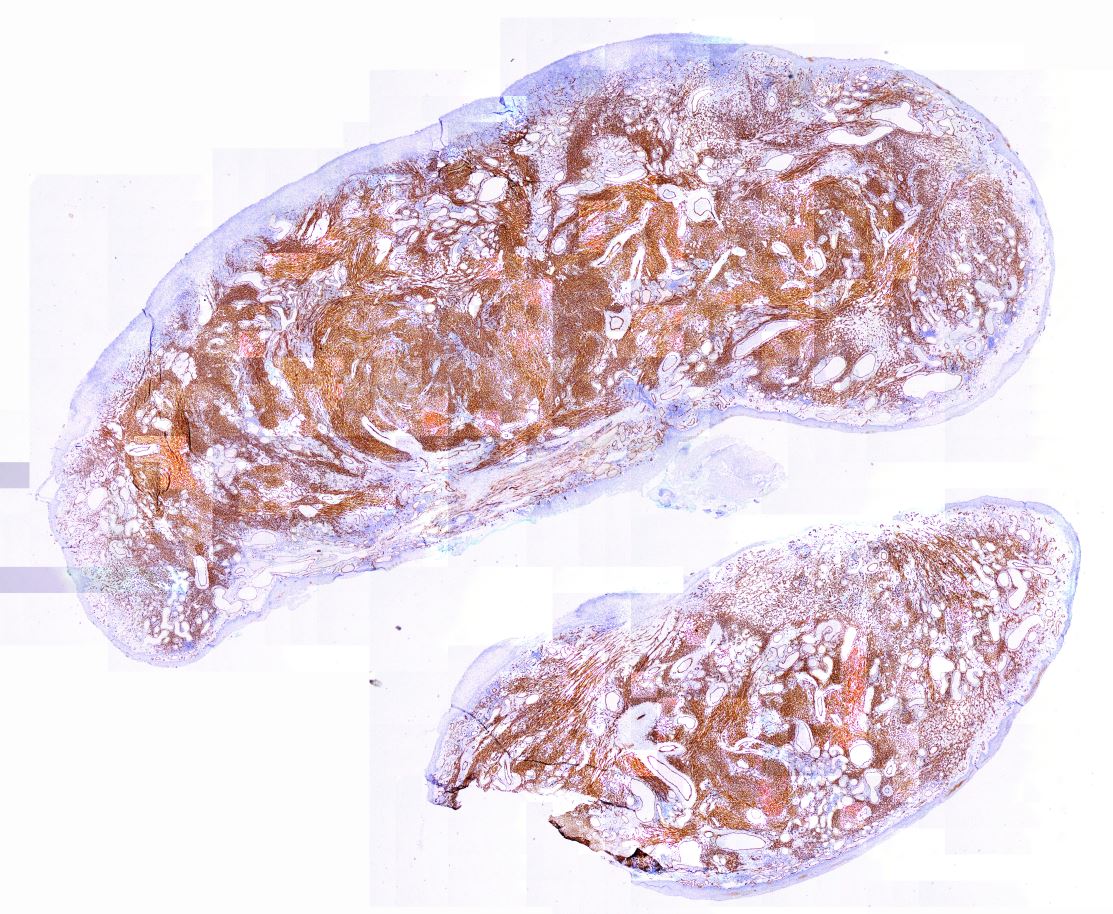

Cribriform-morular thyroid carcinoma Tiroidin nadir tümörü. Belirsiz papiller yapılar, moruller ve tiroglobulin yokluğu. Beta katanin ilişkili.

Cribriform-morular thyroid carcinoma, ikinci odak ile birlikte Çok sayıda odak içeren tümörde iki ayrı tümör odağı

Beta-Catenin pozitifliği, Cribriform-morular thyroid carcinoma Beta-Catenin nükleer ve sitoplazmik pozitiflik.